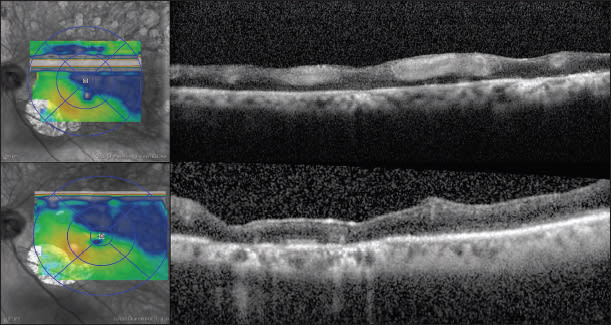

Case 3: A Stitch in Time. A 73-year-old male was referred in May 2010 by an outside retina specialist for treatment of CRVO in both eyes. The right CRVO had occurred in February 2010 and had received two previous bevacizumab injections, and the left CRVO had occurred in April 2010 and had received one bevacizumab injection. On presentation, VA was 20/100 in both eyes, and the examination showed findings consistent with the presenting diagnosis, with SD-OCT confirming CME in the right eye and a relatively compact retina in the left eye (Figures 4 and 5, top) Especially because of the subjective and objective visual acuity, the patient subsequently received subsequent bilateral bevacizumab injections over the next two months. In July 2010, the visual acuity was 20/60 in the right eye and 20/50 in the left eye. The SD-OCT appearance (Figures 4 and 5, middle) demonstrated persistent CME in the right eye, and the same compact appearance to the left macula. Because of the visual improvement and lack of obvious CME on SD-OCT, treatment was deferred for the left eye, though continued for the right eye.

Figure 5. Case 3: SD OCT shows a relatively compact retina in the left eye (top) with a visual acuity of 20/70, and a similar appearance after two intravitreal injections of Avastin (middle) although a VA of 20/50. Treatment was then deferred, but one month later CME reaccumulated and VA dropped to 20/100 (bottom). After continued treatment, the CME decreased and VA was 20/50.